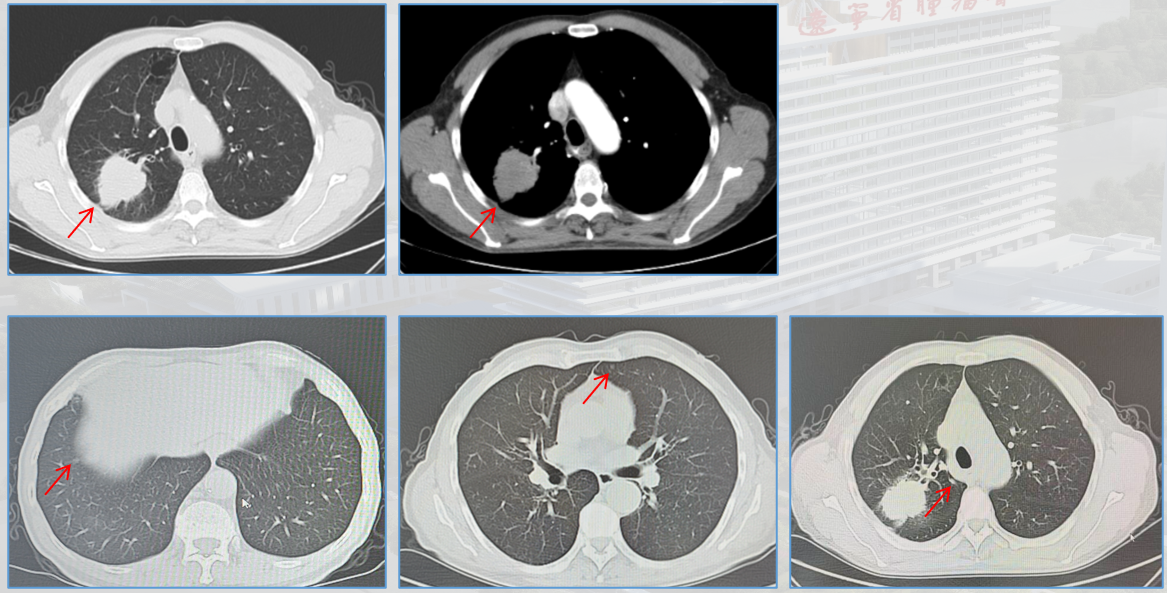

胸部+上腹部增强CT:右肺上叶后段见肿块影,大小约50mmX44mm,可见分叶、毛刺、胸膜凹陷、充气支气管、棘状突起征象,恶性可能大。双肺内多发磨玻璃及实性小结节影,建议随诊观察。右肾小囊肿可能大,建议复查。

右肺上叶恶性肿瘤(腺癌,PD-L1<1%);cT2bN0M0 IIA期;ECOG 1分。

MDT 意见:科室开展 MDT 讨论,影像科排除骨转移,认为肺部结节暂无法定性,建议定期复查,综合团队意见采用新辅助治疗后再行手术的策略。

1、2025.01新辅助治疗:纳武利尤单抗360mg Q3W+培美曲塞+顺铂 Q3W;3周期。